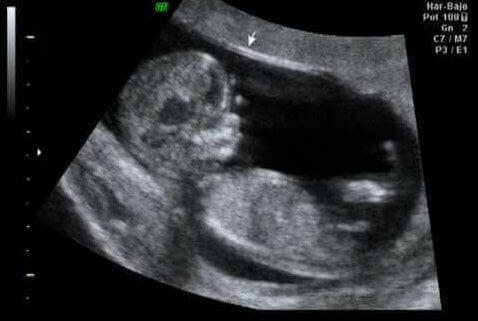

12. raskausviikon ultraäänitutkimus

Raskauden ensimmäisen kolmanneksen kohokohta on usein ensimmäinen kahdesta raskauden aikaisesta ultraäänitutkimuksesta. Ensimmäinen tutkimus suoritetaan 10. ja 13. raskausviikon välillä, ja sen tarkoituksena on:

- Määrittää raskauden kesto. Tutkimuksessa selvitetään, vastaako sikiön koko raskausviikkoja, ja jos ei vastaa, voidaan laskettua aikaa muuttaa.

- Varmistaa sikiöiden määrä. Ultraäänessä tarkistetaan, onko kyseessä monisikiöraskaus.

- Sikiön sydämen sykkeen varmistaminen.

- Sikiön rakenteellisten kehityshäiriöiden havaitseminen, eli varmistetaan sikiön kehittyvän normaalisti.

- Niskaturvotuksen mittaaminen.

- Istukan paikan tutkiminen.

Niskaturvotuksen mittaaminen on tärkeää, sillä se toimii kromosomipoikkeavuuksien riskin osoittajana. Niskaturvotus on yleensä ohimenevää, mutta osassa tapauksista turvotus lisääntyy ja johtaa raskauden keskeytymiseen. Jos sikiöllä havaitaan rakenteellisia kehityshäiriöitä, harkitaan kromosomitutkimuksia.